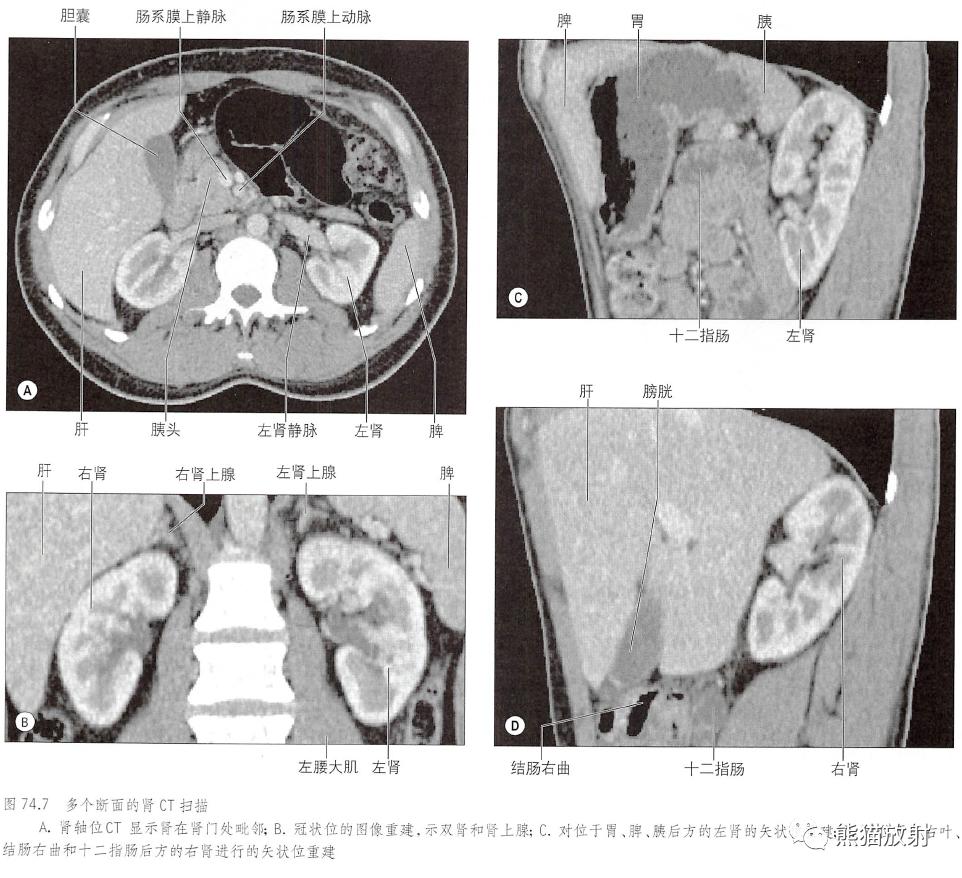

肾CT断面

肾的表面(前后毗邻)